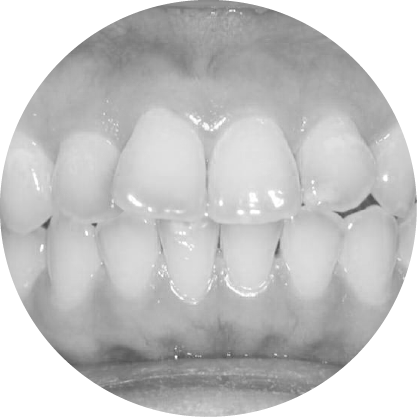

ตัวอย่างในชีวิตจริง

การสบฟันแบบไขว้ (Scissor Bite)

การแก้ไขฟันสบไขว้ เพื่อการสบฟันที่สมมาตร

ฟันสบไขว้คือภาวะที่ฟันบนหนึ่งซี่หรือมากกว่าสบอยู่ด้านในของฟันล่าง ซึ่งอาจทำให้เกิดการสึกของฟันอย่างไม่เท่ากันหรือปัญหาข้อต่อขากรรไกร การจัดฟันช่วยปรับแนวการสบฟันให้ถูกต้อง เพื่อประสิทธิภาพในการใช้งานที่ดีขึ้นและความสมดุลของใบหน้า